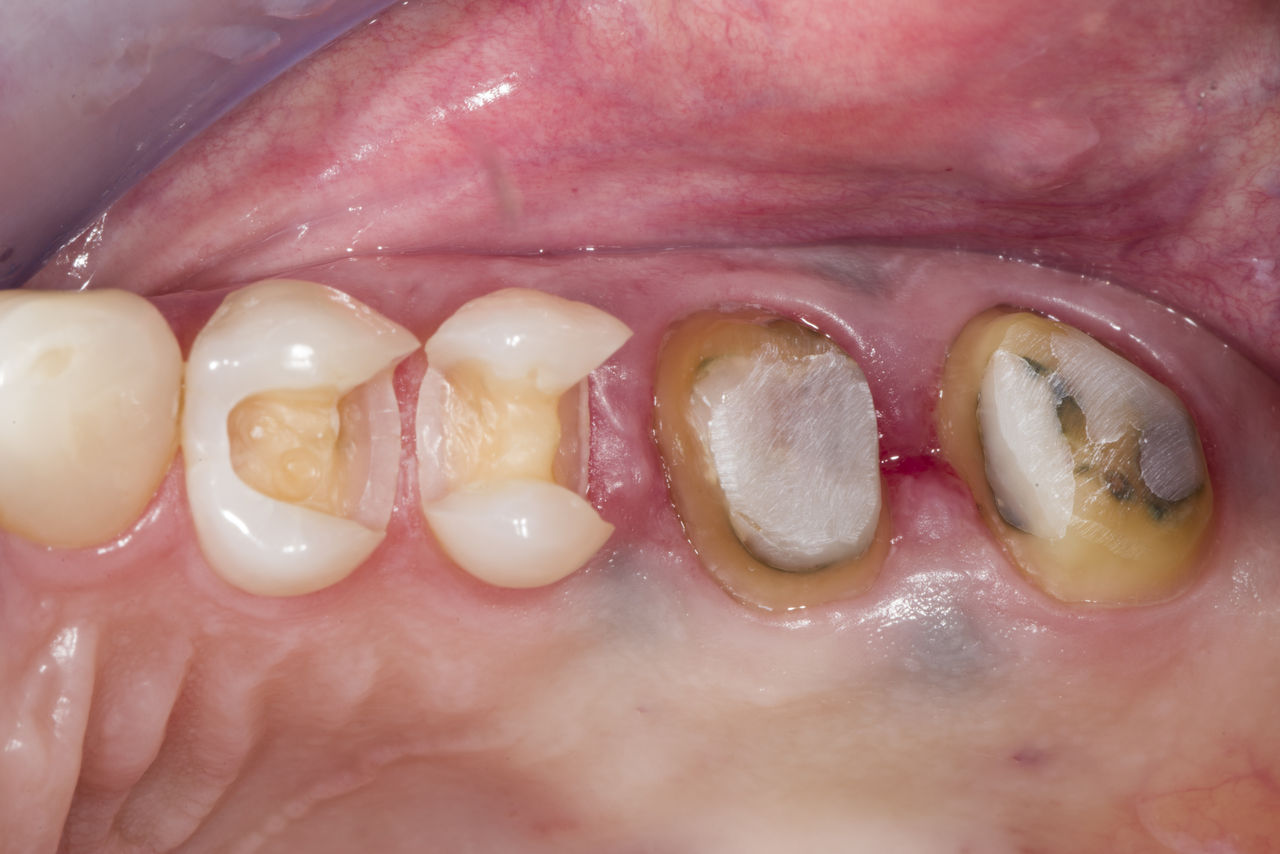

Rehabilitación del cuadrante

Dos coronas CEREC Tessera y dos inlays

En una sola visita de cuatro horas, se realizó la restauración de dos coronas y dos inlays, que tenían 15 años. El paciente quedó muy satisfecho con el muy buen resultado estético.

Antes: Obturaciones insuficientes en el segundo cuadrante. Las restauraciones tenían alrededor de 15 años.

Después: Coronas fabricadas chairside hechas de CEREC Tessera (dientes 26/27). Inlays para los dientes 24 y 25 hechas de bloques de composite.

Dr. Andreas Bindl

Zúrich, Suiza